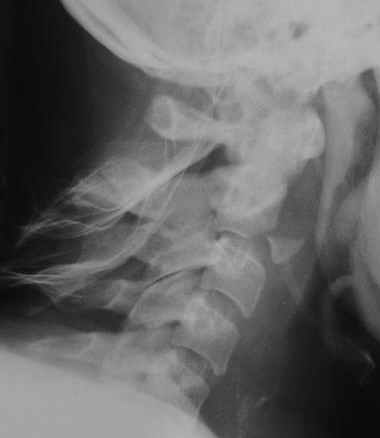

Больная непреглядного вида и образа жизни поступила после ДТП с клиникой перелома С2 без неврологии и внутреннего мыщелка б\берцовой кости.

Михаил Владимирович! На предлагаемых снимках травматическая нестабильность сегмента С2-С3 с отрывом нижнего переднего края С2 и подвывихом его кзади.

Требует уточнения взаимоотношения в дугоотростчатых суставах (сделайте анфас

и косые снимки). Подлежит хирургической стабилизации 100%, и хирургическому

устранению смещения (подвывиха-вывиха). Без этого хроник по голове и кандидат на сосудистое поражение мозга. Социальный статус человеков на

протяжении жизни может меняться неоднократно и в любую сторону, не следует нам на него ориентироваться сильно. Отдайте вертебрологам.